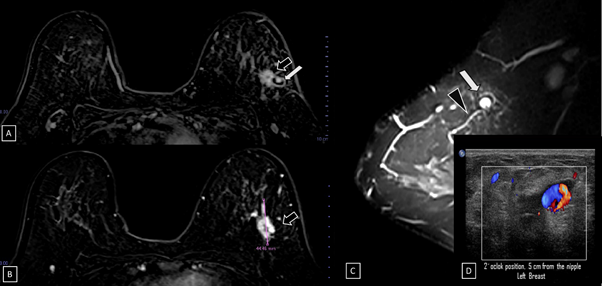

29-years-old woman has been diagnosed with carcinoma by core needle biopsy recently performed in the left breast. She attends our department due to a pulsatile and palpable mass in the site of the biopsy. By mammography, in craniocaudal (CC) and mediolateral Oblique (OML) projections, the breast tissue is the heterogeneously dense (category “C” of the American College of Radiology, 2013). In the left breast, exists a focal asymmetry associated with residual cluster of amorphous microcalcifications and architectural distortion, localized in the middle third of the upper outer quadrant that coincides with the site of the biopsy. Adjacent to these findings, at the superior region, a new nodule is observed. This nodule is isodense, round and with microlobulated margins, which corresponds to the palpable area which is signaling by triangular tissue marker. In the ipsilateral axillary region, an anormal lymph node is seen (Figure 1). In the MLO and electronic magnification of MLO projection, the nodule and the residual calcifications are clearly visible (Figure 2). By Digital breast tomosynthesis (DBT) in CC and MLO projections, the margins of the nodule are well defined, and the architectural distortion is confirmed (Figure 3 and 4). By ultrasound, in the left breast, we find a 1.3 cm, circumscribed, oval, hypoechoic nodule with thin wall and echogenic ring, located at 2 o'clock position, 5 cm from the nipple, nearby the site of the biopsy. Color Doppler demonstrates bidirectional vascularity within the nodule termed “the yin-yang sign” (Figure 5). Subtraction MR imaging shows spiculated, irregular, and heterogenous enhancement nodule, which corresponds to the malignant tumor. Adjacent to the primary tumor, the T2-weighted sequence shows a round and circumscribed nodule. This nodule and its nutrient vessel are isointense to water (Figure 6). In this case, left mastectomy and sentinel lymph node biopsy is indicated. The primary tumor and PSA are surgically removed. At the present time, the patient has metastatic lesion in the brain.

Figure 5A) Gray-scale ultrasound image. In the left breast, a 1.3 cm, circumscribed, oval, hypoechoic nodule with thin wall and echogenic ring is seen at 2 o'clock position, 5 cm from the nipple, nearby the site of the biopsy. B) Color Doppler image. The nodule demonstrates bidirectional vascularity within it, termed “the yin-yang sign”.

Figure 6 Subtraction MR imaging.

A) and B) A spiculated, irregular, and heterogenous enhancement nodule is observed, which corresponds to the malignant tumor (black arrow).

C) T2-weighted sequence image. Adjacent to the primary tumor, a round and circumscribed nodule is identified. This nodule (white arrow) and its nutrient vessel (black head arrow) are isointense to water.

D) Color Doppler image. The yin-yang sign is shown withing the nodule.